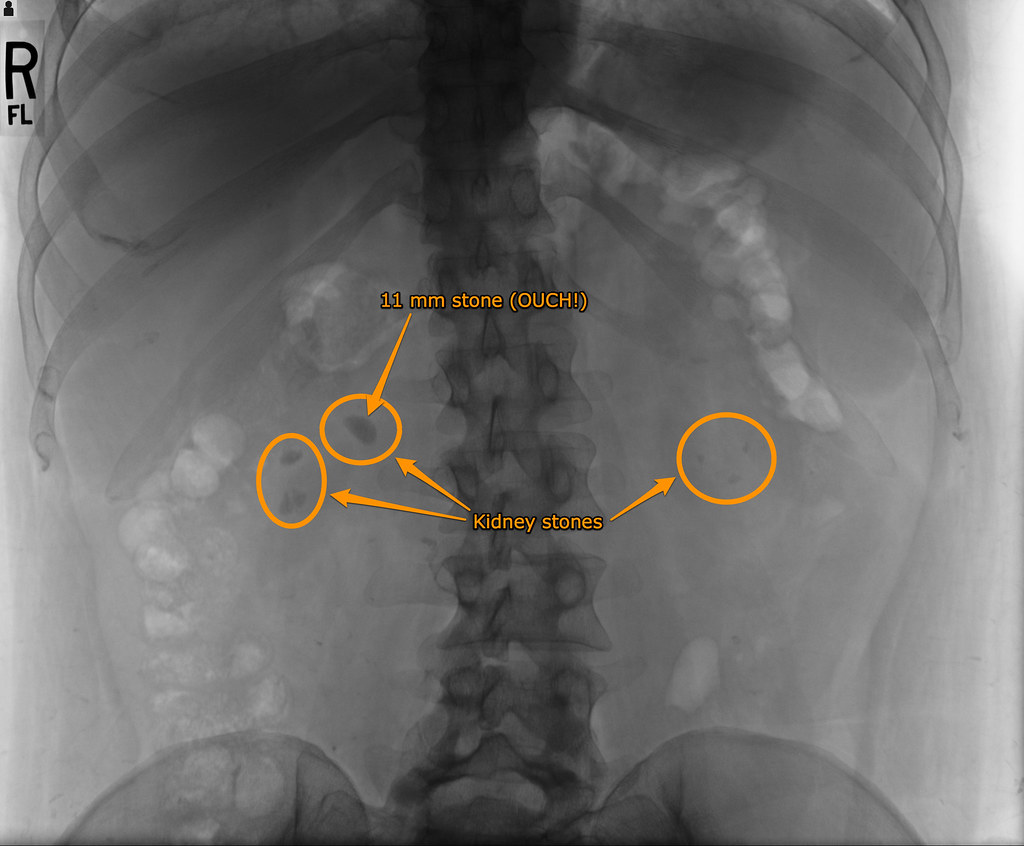

Tiny stones are less likely to become stuck in the kidneys or other parts of the urinary tract. The stones are broken into tiny pieces. Mar 25, 2021 · kidney stone symptoms. I had a 8mm stone removed by lithotripsy 2 months ago. But, when it starts to move or becomes very large, you may have symptoms.

Shock waves from outside the body are targeted at a kidney stone causing the stone to fragment. When symptoms do occur, they usually come on suddenly and include excruciating cramping pain in the low back and/or abdomen, side, or groin. Symptoms of a kidney stone include: However whey they do occur they include shortness of breath, generalized swelling, and congestive heart failure. Some people have symptoms of kidney failure while others do not; Mar 25, 2021 · kidney stone symptoms. Diagnosis the only way to know for sure that you have a kidney stone is to see a doctor so they can make a diagnosis. Mar 02, 2020 · kidney stones vary in size.

What are the symptoms of kidney stones? Lt is sometimes called eswl: Kidney stones that do not produce symptoms are called silent stones. I had a 8mm stone removed by lithotripsy 2 months ago. Feb 20, 2018 · i spent months in inpatient treatment for anxiety. Kidney stones form within the kidney or urinary tract. Report said it was 60% carbonate apatite, 30% calcium oxalate dihydrate and 10% calcium oxalate mono hydrate. The stones are broken into tiny pieces. But, when it starts to move or becomes very large, you may have symptoms. When symptoms do occur, they usually come on suddenly and include excruciating cramping pain in the low back and/or abdomen, side, or groin. Shock waves from outside the body are targeted at a kidney stone causing the stone to fragment. Feb 12, 2021 · kidney (renal) failure (acute or chronic) occurs when the kidneys no longer function well and the end stage of kidney failure. Shock wave lithotripsy (swl) is the most common treatment for kidney stones in the u.s.